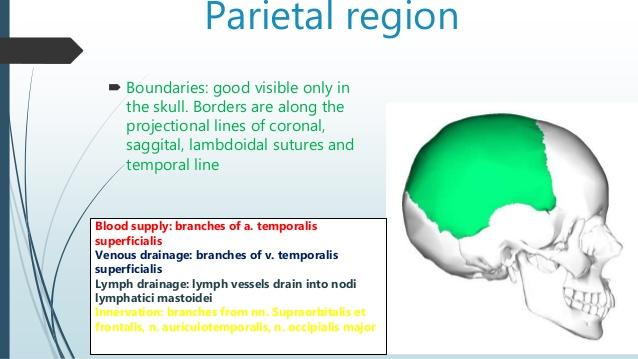

"parietal region":

https://www.slideshare.net/rustamsultonov/topographic-anatomy-of-the-brain-and-brain-part-of-the-skull

"chiefly the parietal bone"

chiefly:

mainly or mostly, but not completely